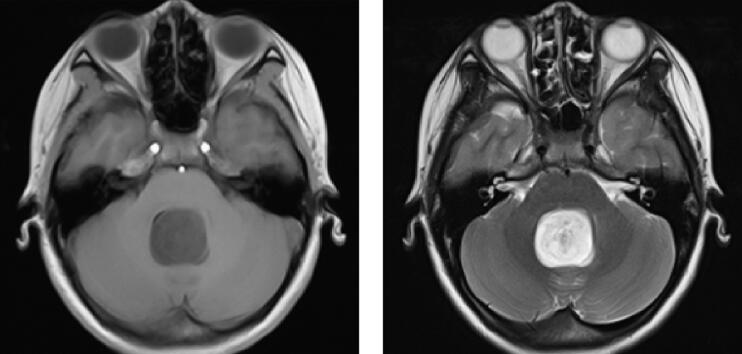

扫描应用3.0T超导型MRI仪(Siemens Magnetom Trio Tim),8通道头部线圈,患者取仰卧位,头先进。应用体轴横断位T1WI(TR/TE=500ms/8.9ms,5mm层厚)、T2WI(TR/TE=4500ms/87ms,5mm层厚)。应用钆喷酸葡胺(Gd-DTPA)注射液20ml,经手背静脉以高压注射器4ml/s流率注入,随之以0.9%生理盐水20ml冲入,4分钟后扫描。MRI表现见图1。

图1 第四脑室毛细胞星形细胞瘤:MRI平扫第四脑室内类圆形异常信号,T2WI呈高信号,T1WI呈低信号,增强后强化明显,呈花环样强化